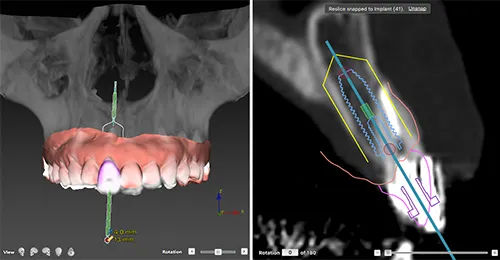

診査、診断、ラジオグラフィックガイドを作成後、CTにて3D分析。

サージカルガイドを用いたインプラント埋入術を行う方針に決定。

3Dプランニング

スマートフュージョンでの分析結果